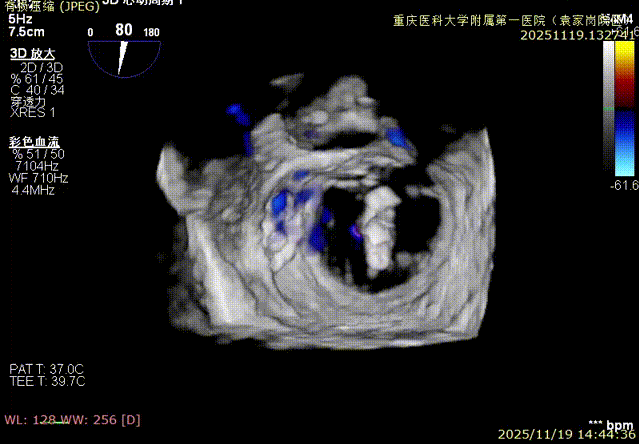

视频3:二尖瓣三维视图

图1、图2:2区瓣叶长度(前叶长度2.46cm,后叶长度1.15cm)及彩色血流